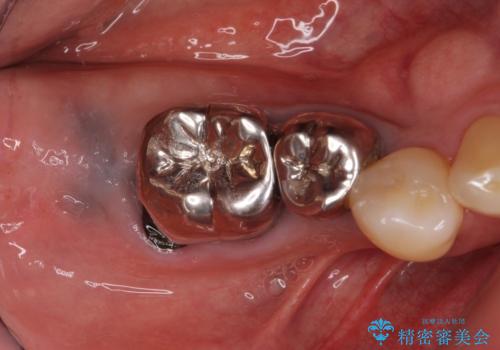

不適な樹脂の詰め物 被せ物で被覆

担当医 岡田康成